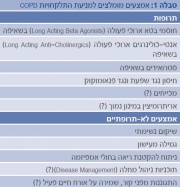

| 21:39, 5 במרץ 2015 | AsthmaCOPD4.jpg (קובץ) |  |

247 קילו־בייטים | Motyk | 1 | |

| 21:29, 5 במרץ 2015 | AsthmaCOPD3.jpg (קובץ) |  |

380 קילו־בייטים | Motyk | 1 | |

| 08:57, 5 במרץ 2015 | AsthmaCOPD2.jpg (קובץ) |  |

582 קילו־בייטים | Motyk | 1 | |

| 08:31, 5 במרץ 2015 | AsthmaCOPD1.jpg (קובץ) |  |

56 קילו־בייטים | Motyk | 1 | |